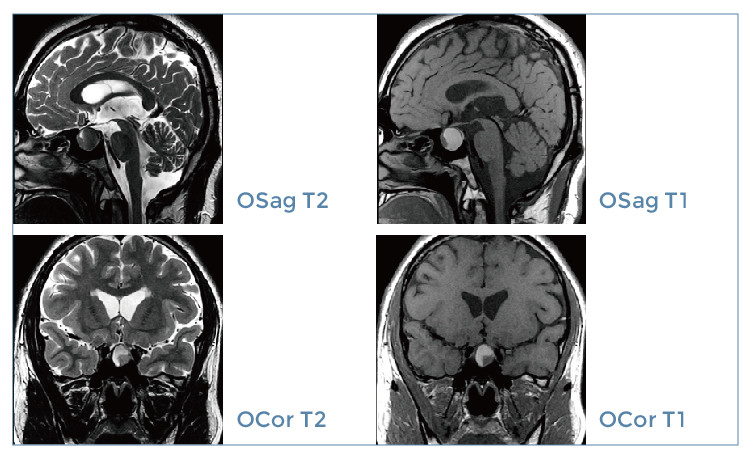

【朗润影像档案】磁共振影像病例分享(编号20191229)